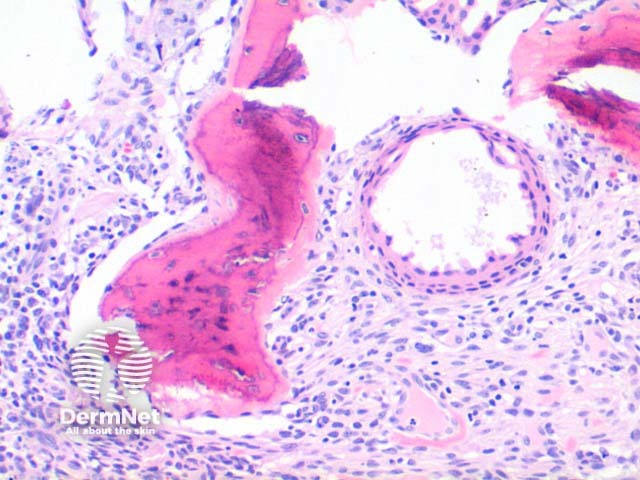

Scanning power of osteoma cutis reveals the presence of dense eosinophilic deposits in the dermis or subcutaneous tissue (Figure 1). Spicules of bone may be seen to perforate the epidermis in the process of transepidermal elimination (Figures 2 and 3). Most cutaneous bone formation occurs by the process of membranous ossification and so associated cartilage tissue is lacking. Bone is identified by osteocytes held within small lacunae (Figures 4 and 5) and the hydroxyapatite eosinophilic support material. In larger deposits, Haversian systems can be seen as concentric osteocytes around a central blood vessel (carried within a Haversian canal).

Figure 2